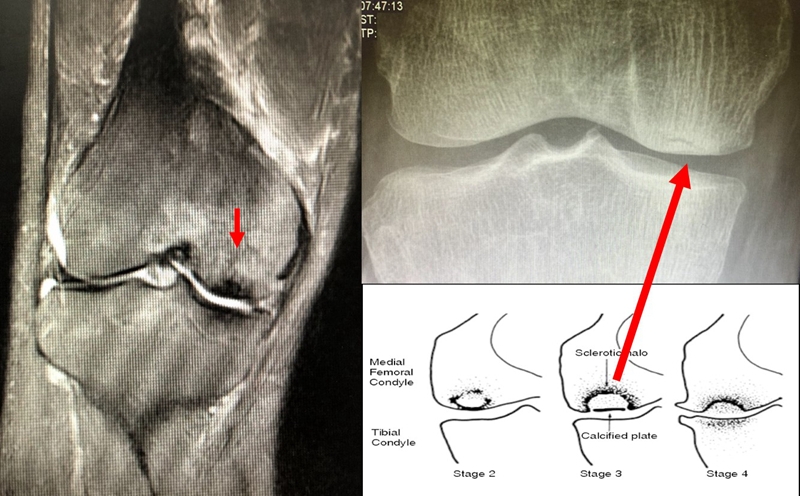

目前SONK诊断最常用的分期方法是1979年Koshino提出的分期法。Koshino分期基于临床和影像学的结果,将SONK分为四个阶段:

Ⅰ期:患者有膝关节症状,但影像学正常;

Ⅱ期:X线显示负重区变平,软骨下信号升高,周围有骨硬化;

Ⅲ期:受影响区域扩大和软骨下塌陷;

Ⅳ期:病变周围骨硬化和髁突周围骨赘形成的退行性阶段。

1979年Koshino分期